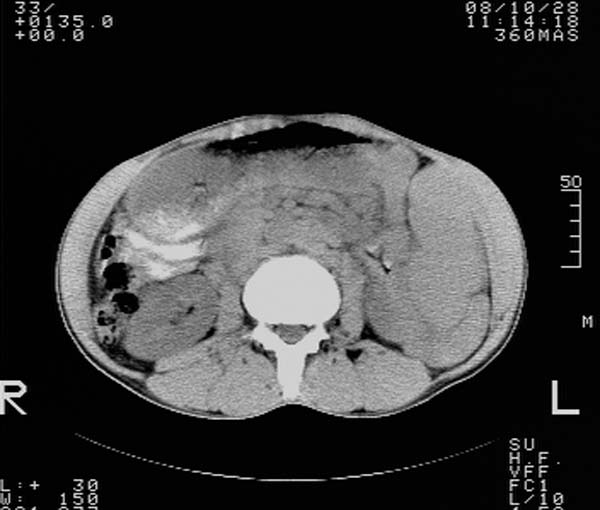

m,65y。半年前发现颈小结节,逐渐增多增大,现双侧耳后、颌下及颈部表浅淋巴肿大。胸片示双肺门增大。外院曾穿刺诊断为淋巴结核。在我科作胸腹部ct,我们觉得外院病检有误。现将图像上传请战友讨论。

纵隔内及腹膜后广泛淋巴结肿大,脾大,肝内似可见低密度影,结合病史半年前发现颈小结节,逐渐增多增大,现双侧耳后、颌下及颈部表浅淋巴肿大。考虑淋巴瘤。

我们也是首先考虑淋巴瘤。只是外院病检报告是结核。让人迷惑。肝左叶多发低密度占位,没增强不好定论。

纵隔,双肺门腹膜后多发淋巴结重大,非融合,肝脾轻度肿大,双肺野弥漫性小结节;考虑淋巴瘤,结节病可能性

纵隔内,双肺门、腋窝及腹膜后多发肿大淋巴结影,肺内小结节影,肝脾体积增大,支持淋巴瘤。肝内多发低密度影,考虑小囊肿。

考虑淋巴瘤肺、肝内转移,脾脏肿大。

纵隔内,双肺门、腹膜后多发肿大淋巴结影及颈部淋巴结肿大,肝脾体积大.结合临床,淋巴瘤可能性大。